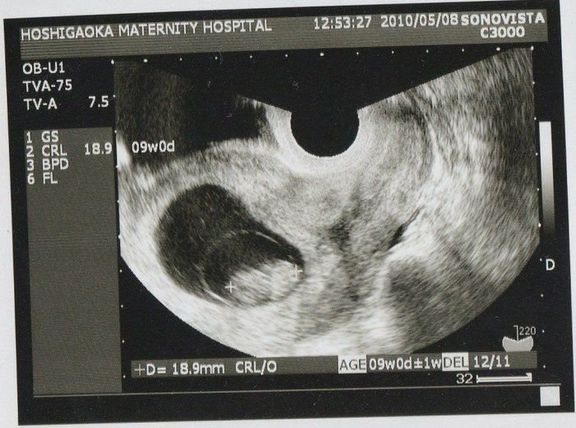

"おなかの中はどうなっていくの? エコー写真で振り返る、高齢ママのはじめての妊娠生活" -

待望の妊娠判明!エコー写真に見る、我が子を胸に抱くまでの“命の軌跡275日” -